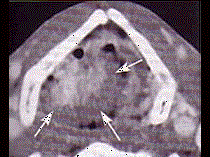

问题 男,60岁,因吞咽疼痛伴咽异物感一个月就诊。间接喉镜下检查发现会厌侧面轻度糜烂、不光滑、隆起,既往有吸烟史。 CT检查见下图,进一步的检查是 ( )

选项 A、放疗 B、活检送病理 C、密切观察 D、抗生素治疗 E、纤维喉镜检查以明确病变范围

答案 B